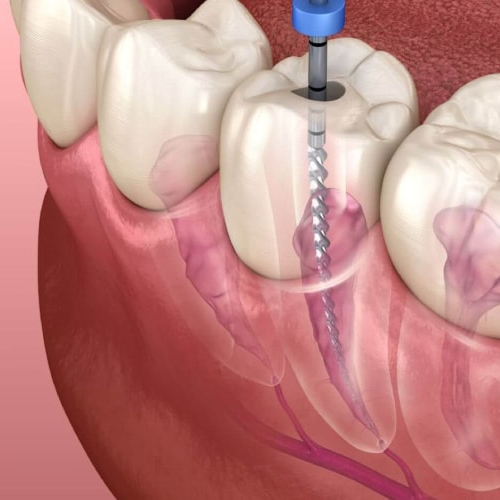

Root Canal Treatment

Relieves pain fast and saves your natural tooth with a smooth, comfortable procedure.